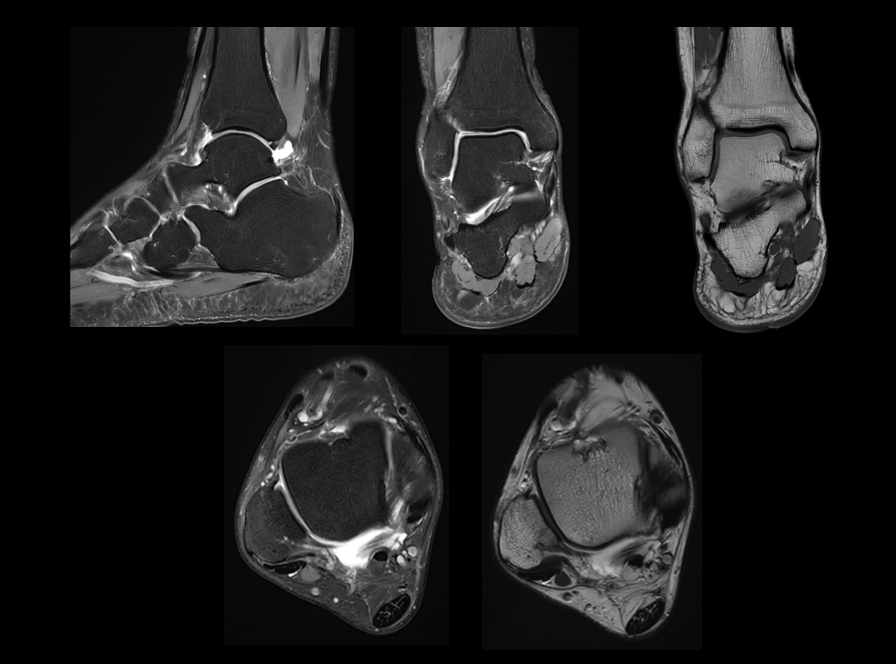

新一代数字化射频系统,实现单视野单次扫描最高达72+通道成像。

高密度线圈组

联影第二代高密线圈,全身成像密度提升超过50%